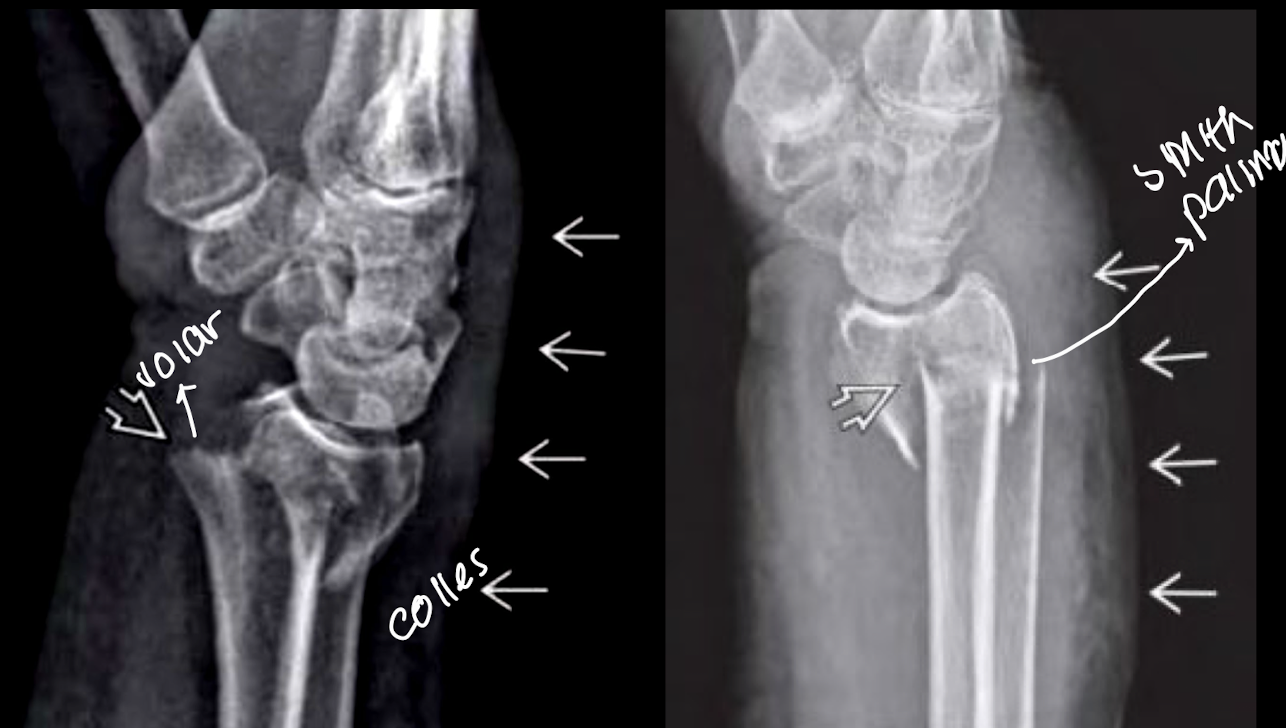

Fx de colles y smith

por caídas

deformidad

edema

dolor

Colles datos importantes

• Caída con mano extendida

• Más común

• fx en extensión

• desviación dorsal de la epifisis radial

• caída con mano abierta

• asx a osteoporosis

• mujeres >40a

Datos smith

fx en flexión (caída sobre el dorso)

desviación volar de la epifisis radial

rara

Colles y smith RX